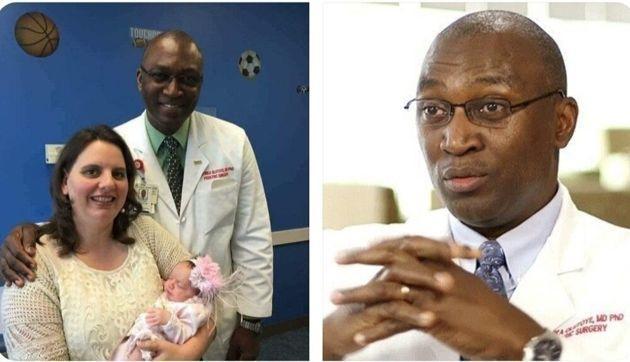

Большинство врачей сходились во мнении, о необходимости прерывания беременности, при этом ребенок однозначно должен был погибнуть. Однако доктор Даррелл Касс, доцент кафедры хирургии, педиатрии, акушерства и гинекологии в медицинском колледже Бейлора предложил еще один вариант — очень рискованный, но дающий ребенку шансы на выживание, хоть и очень небольшие: провести операцию на плоде.

Хирурги вскрыли матку матери и прооперировали ребенка, удалив большую часть опухоли, после чего вернули плод в утробу и зашили. Во время операции сердце малышки останавливалось, но команде врачей удалось запустить его вновь, также потребовалось и переливание крови. Сложнейшая операция длилась более 5 часов.

После перенесенной операции до конца беременности женщина находилась на постельном режиме под пристальным наблюдением врачей. Так ей удалось вынашивать Линли еще 12 недель — малышка родилась во второй раз на 36-й неделе с помощью кесарева сечения.

После рождения девочку ждало еще одно испытание: на 8-й день ей сделали еще одну операцию, во время нее хирурги удалили те участки опухоли, до которых не смогли добраться в первый раз. Через несколько недель Линли полностью поправилась и была выписана домой.